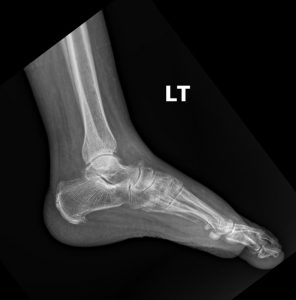

Fig. 2 Lateral view of the foot

Standard plain film radiography is the cornerstone of diagnosis for a suspected lateral malleolar fracture. A proper ankle series must include at least three views to fully assess the bone and joint integrity:

2. Lateral View: A side view that is excellent for visualizing the anterior and posterior aspects of the tibia, the talus, and the calcaneus. It is the best view for identifying posterior malleolar fractures and assessing for any anterior or posterior displacement of the talus.